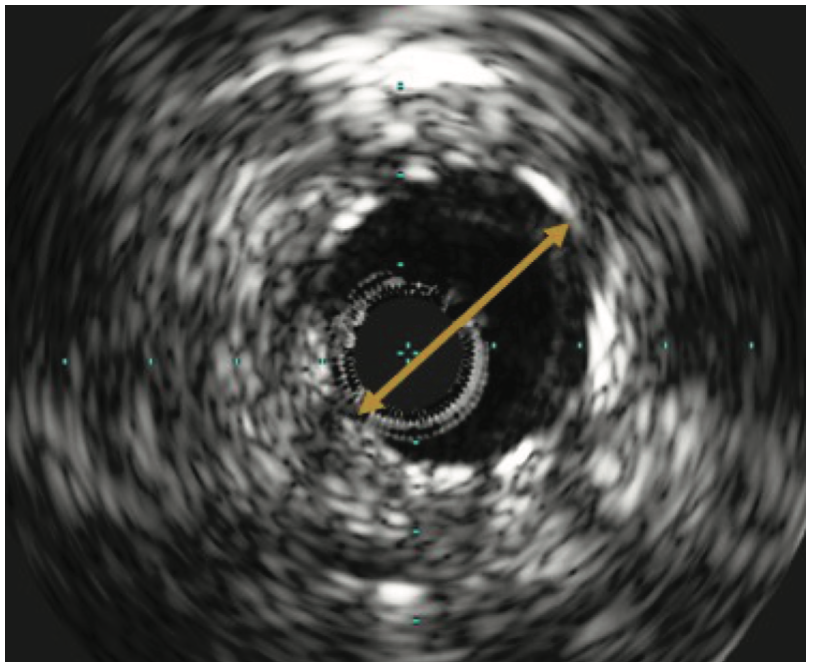

There was also mild to moderate non-obstructive disease of the SVG to the right PDA. The ostial LIMA lesion was validated with the administration of intracoronary nitroglycerin and later with intravascular ultrasound (IVUS) (Figure 1B), as well as by the observation of severe balloon compression during the interventional procedure, as described below.

The native proximal left circumflex artery (TIMI-2 flow pre, type C lesion) had diffuse calcification with a 95% stenosis that was treated successfully with a Diamondback 360˚ coronary orbital atherectomy system (CSI), balloon angioplasty, and Shockwave intravascular lithotripsy with a 3.5 mm x 12 mm C2 balloon using 30 pulses, followed by placement of a Resolute Onyx 3.5 x 26 mm DES (Medtronic) extending back into the left main, and post dilated to >4 mm at high pressure, resulting in 0% residual stenosis with TIMI-3 flow. The OM2 had a 100% functionally occluded competitive vein graft with tortuous flow that was treated successfully with orbital atherectomy, balloon angioplasty, and placement of a Resolute Onyx 2.75 x 26 mm DES extending into the proximal circumflex. The stent was post dilated to high pressure with 0% residual stenosis and TIMI-3 flow post intervention (Figure 4). Intravascular ultrasound (IVUS) was employed for optimal equipment and stent sizing. IVUS also reaffirmed the true significant lesion in the ostia LIMA (Figure 1B, Figure 3B). The patient tolerated the procedure well and was transferred back to general cardiology care, with the addition of aspirin and ticagrelor to her previous medications.

As previously described, arterialization of a venous graft6 with calcium deposition in the vessel wall rather than a plaque may be a case where IVL is preferable over atherectomy. Our case represented an arterial conduit with severe calcification in the vessel wall mixed with soft plaque within the vessel (Figure 1B), in a location where rotational and orbital atherectomy would be ill-advised and potentially compromise the safety of the patient. Intravascular lithotripsy provided effective and safe yielding of the lesion in a LIMA segment with ultimate, optimal DES deployment and expansion.